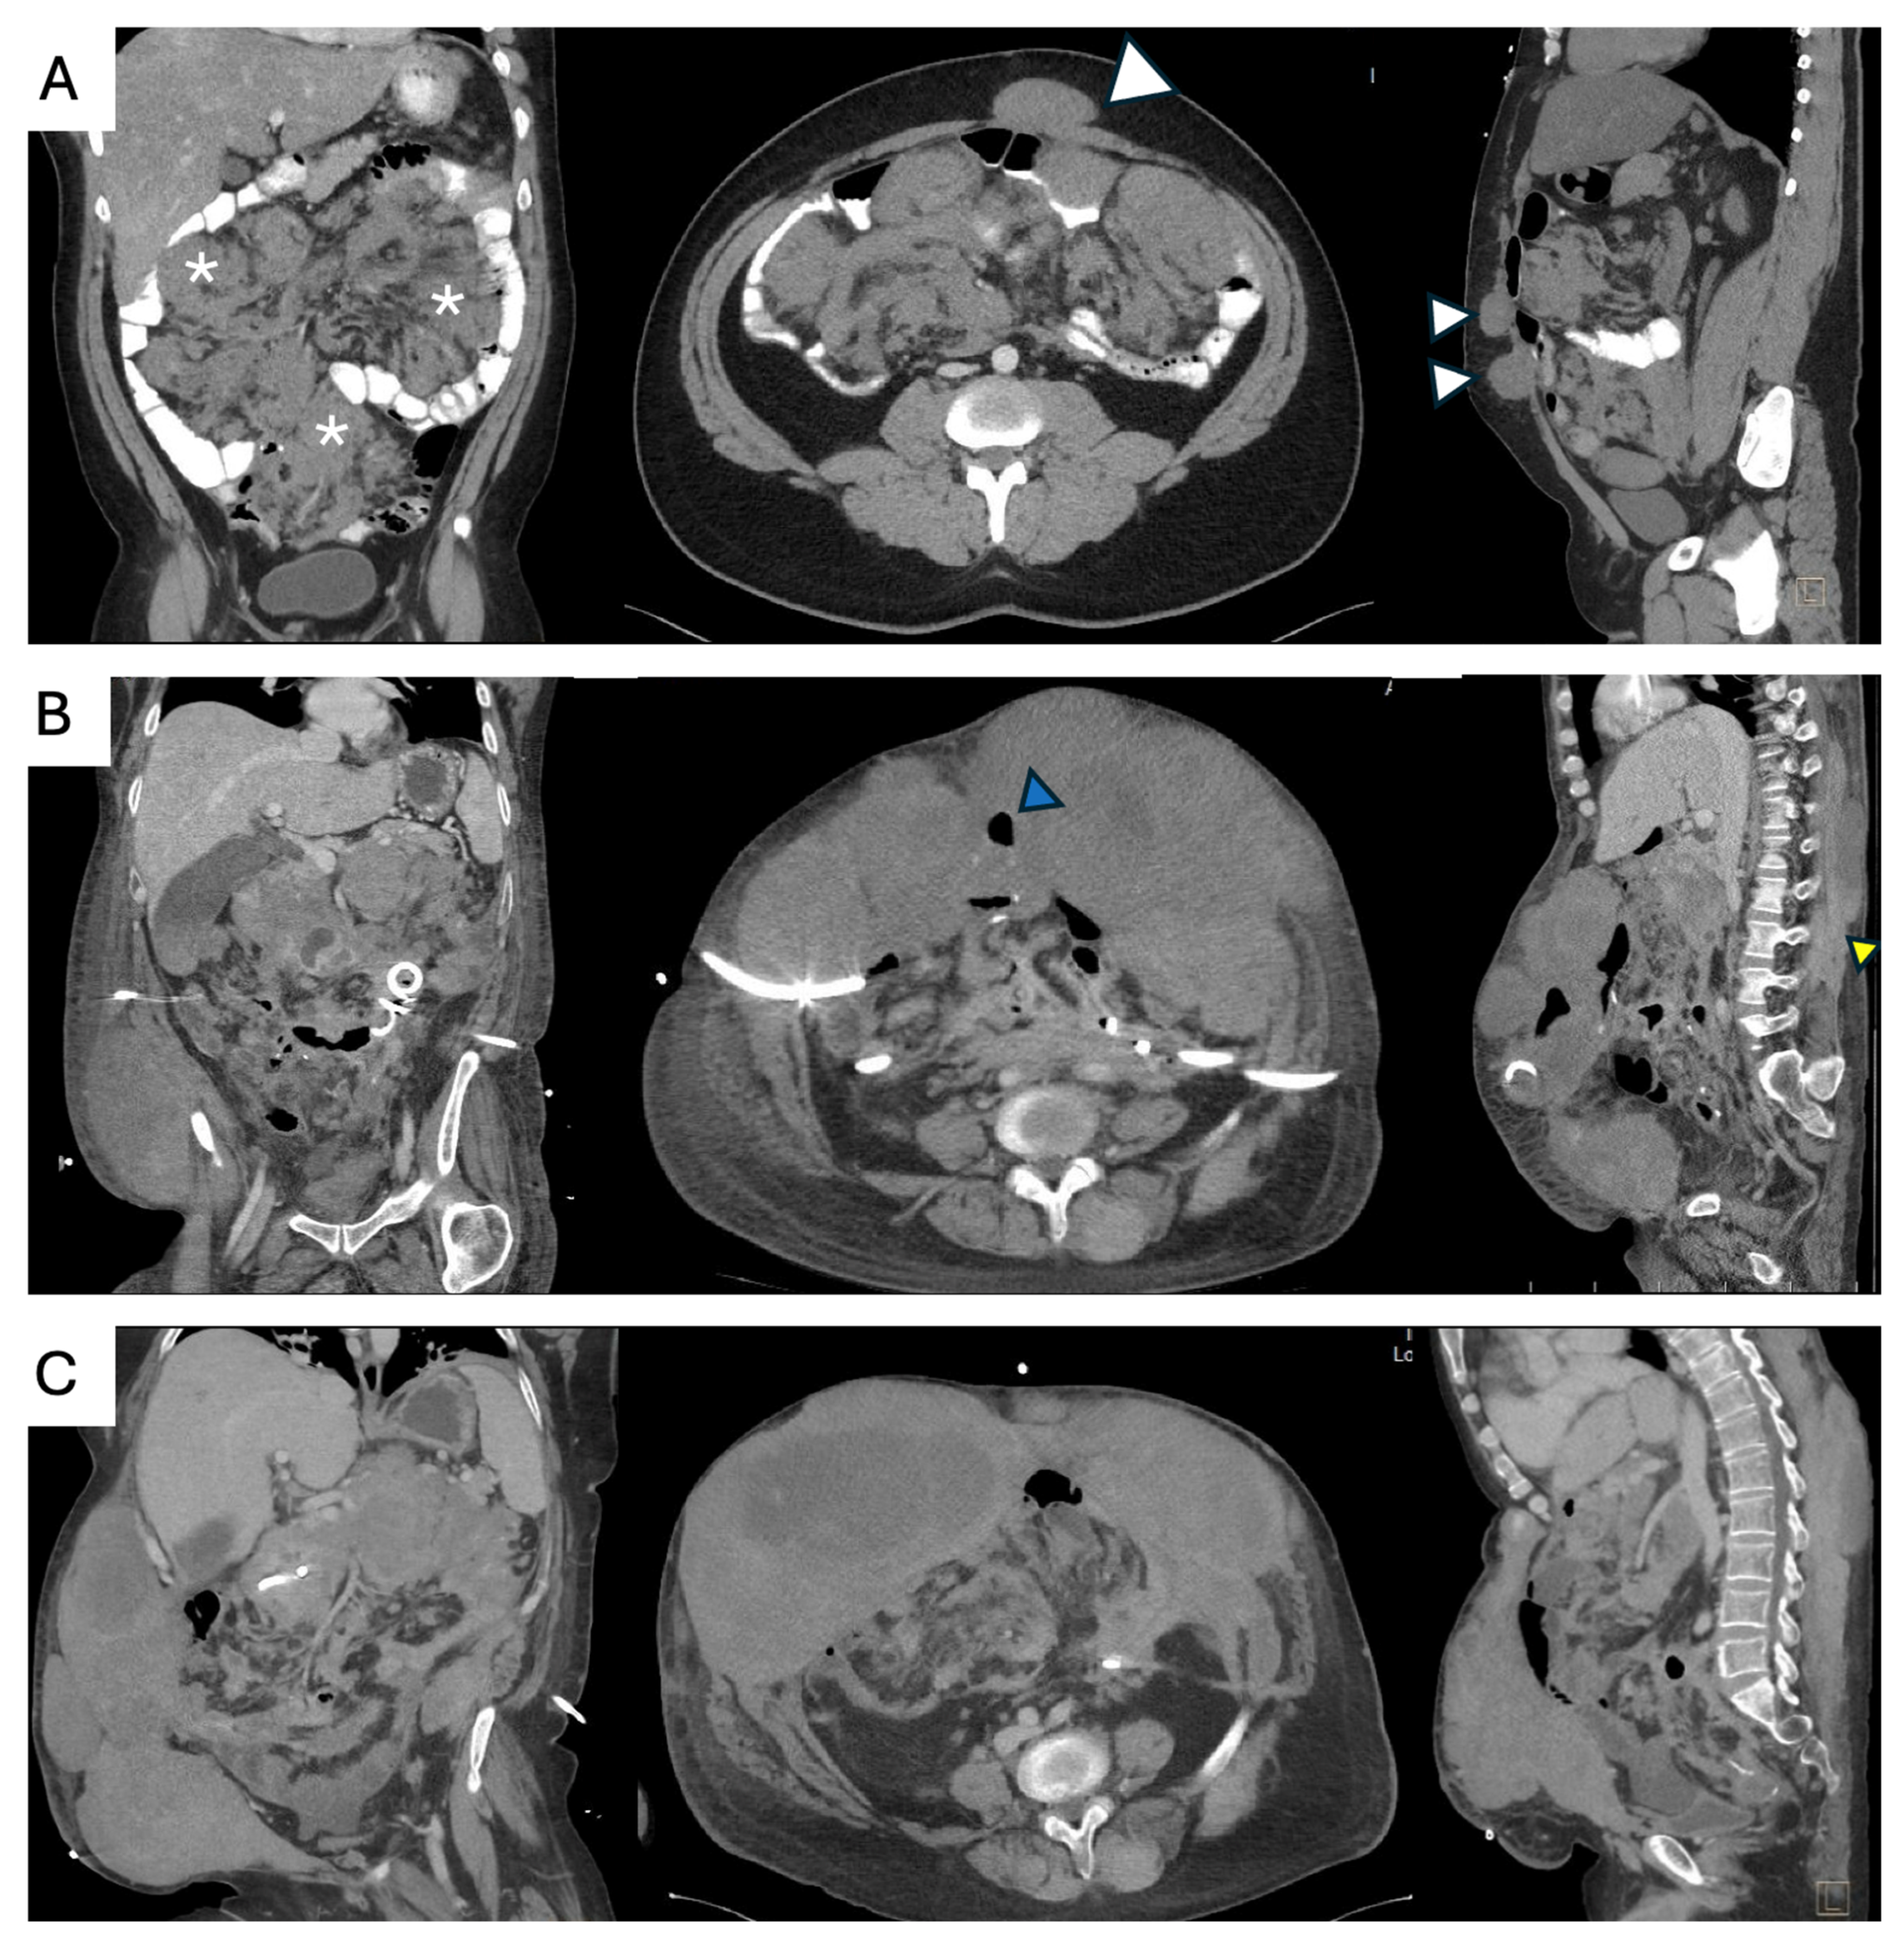

5. Sporadic Intra-Abdominal Desmoids

- Elective resection as primary treatment. In patients with resectable primary disease and low anticipated morbidity, complete macroscopic clearance can be achieved (Figure 3) with favorable operative outcomes in specialist centers [62]. When assessing resectability, key considerations include mesenteric vasculature involvement, anticipated length of small bowel and/or colonic resection, risk of short gut syndrome, and additional visceral involvement. The potential for future tumor growth and associated complications must also be carefully weighed [20,59]. In case of prior incomplete resection and evidence of residual disease, AS is recommended due to the possibility of an indolent course [63].

- Surgical management of complications. Sporadic IA DTs may be associated with complications such as bowel obstruction, perforation, bleeding, or intestinal ischemia in up to 10% of cases [64]. These complications can arise at initial presentation, during AS, or active treatment. Treatment should be guided by the patient’s clinical condition, type and severity of the complication, extent and resectability of the underlying disease, and compounded surgical morbidity. Management options include: